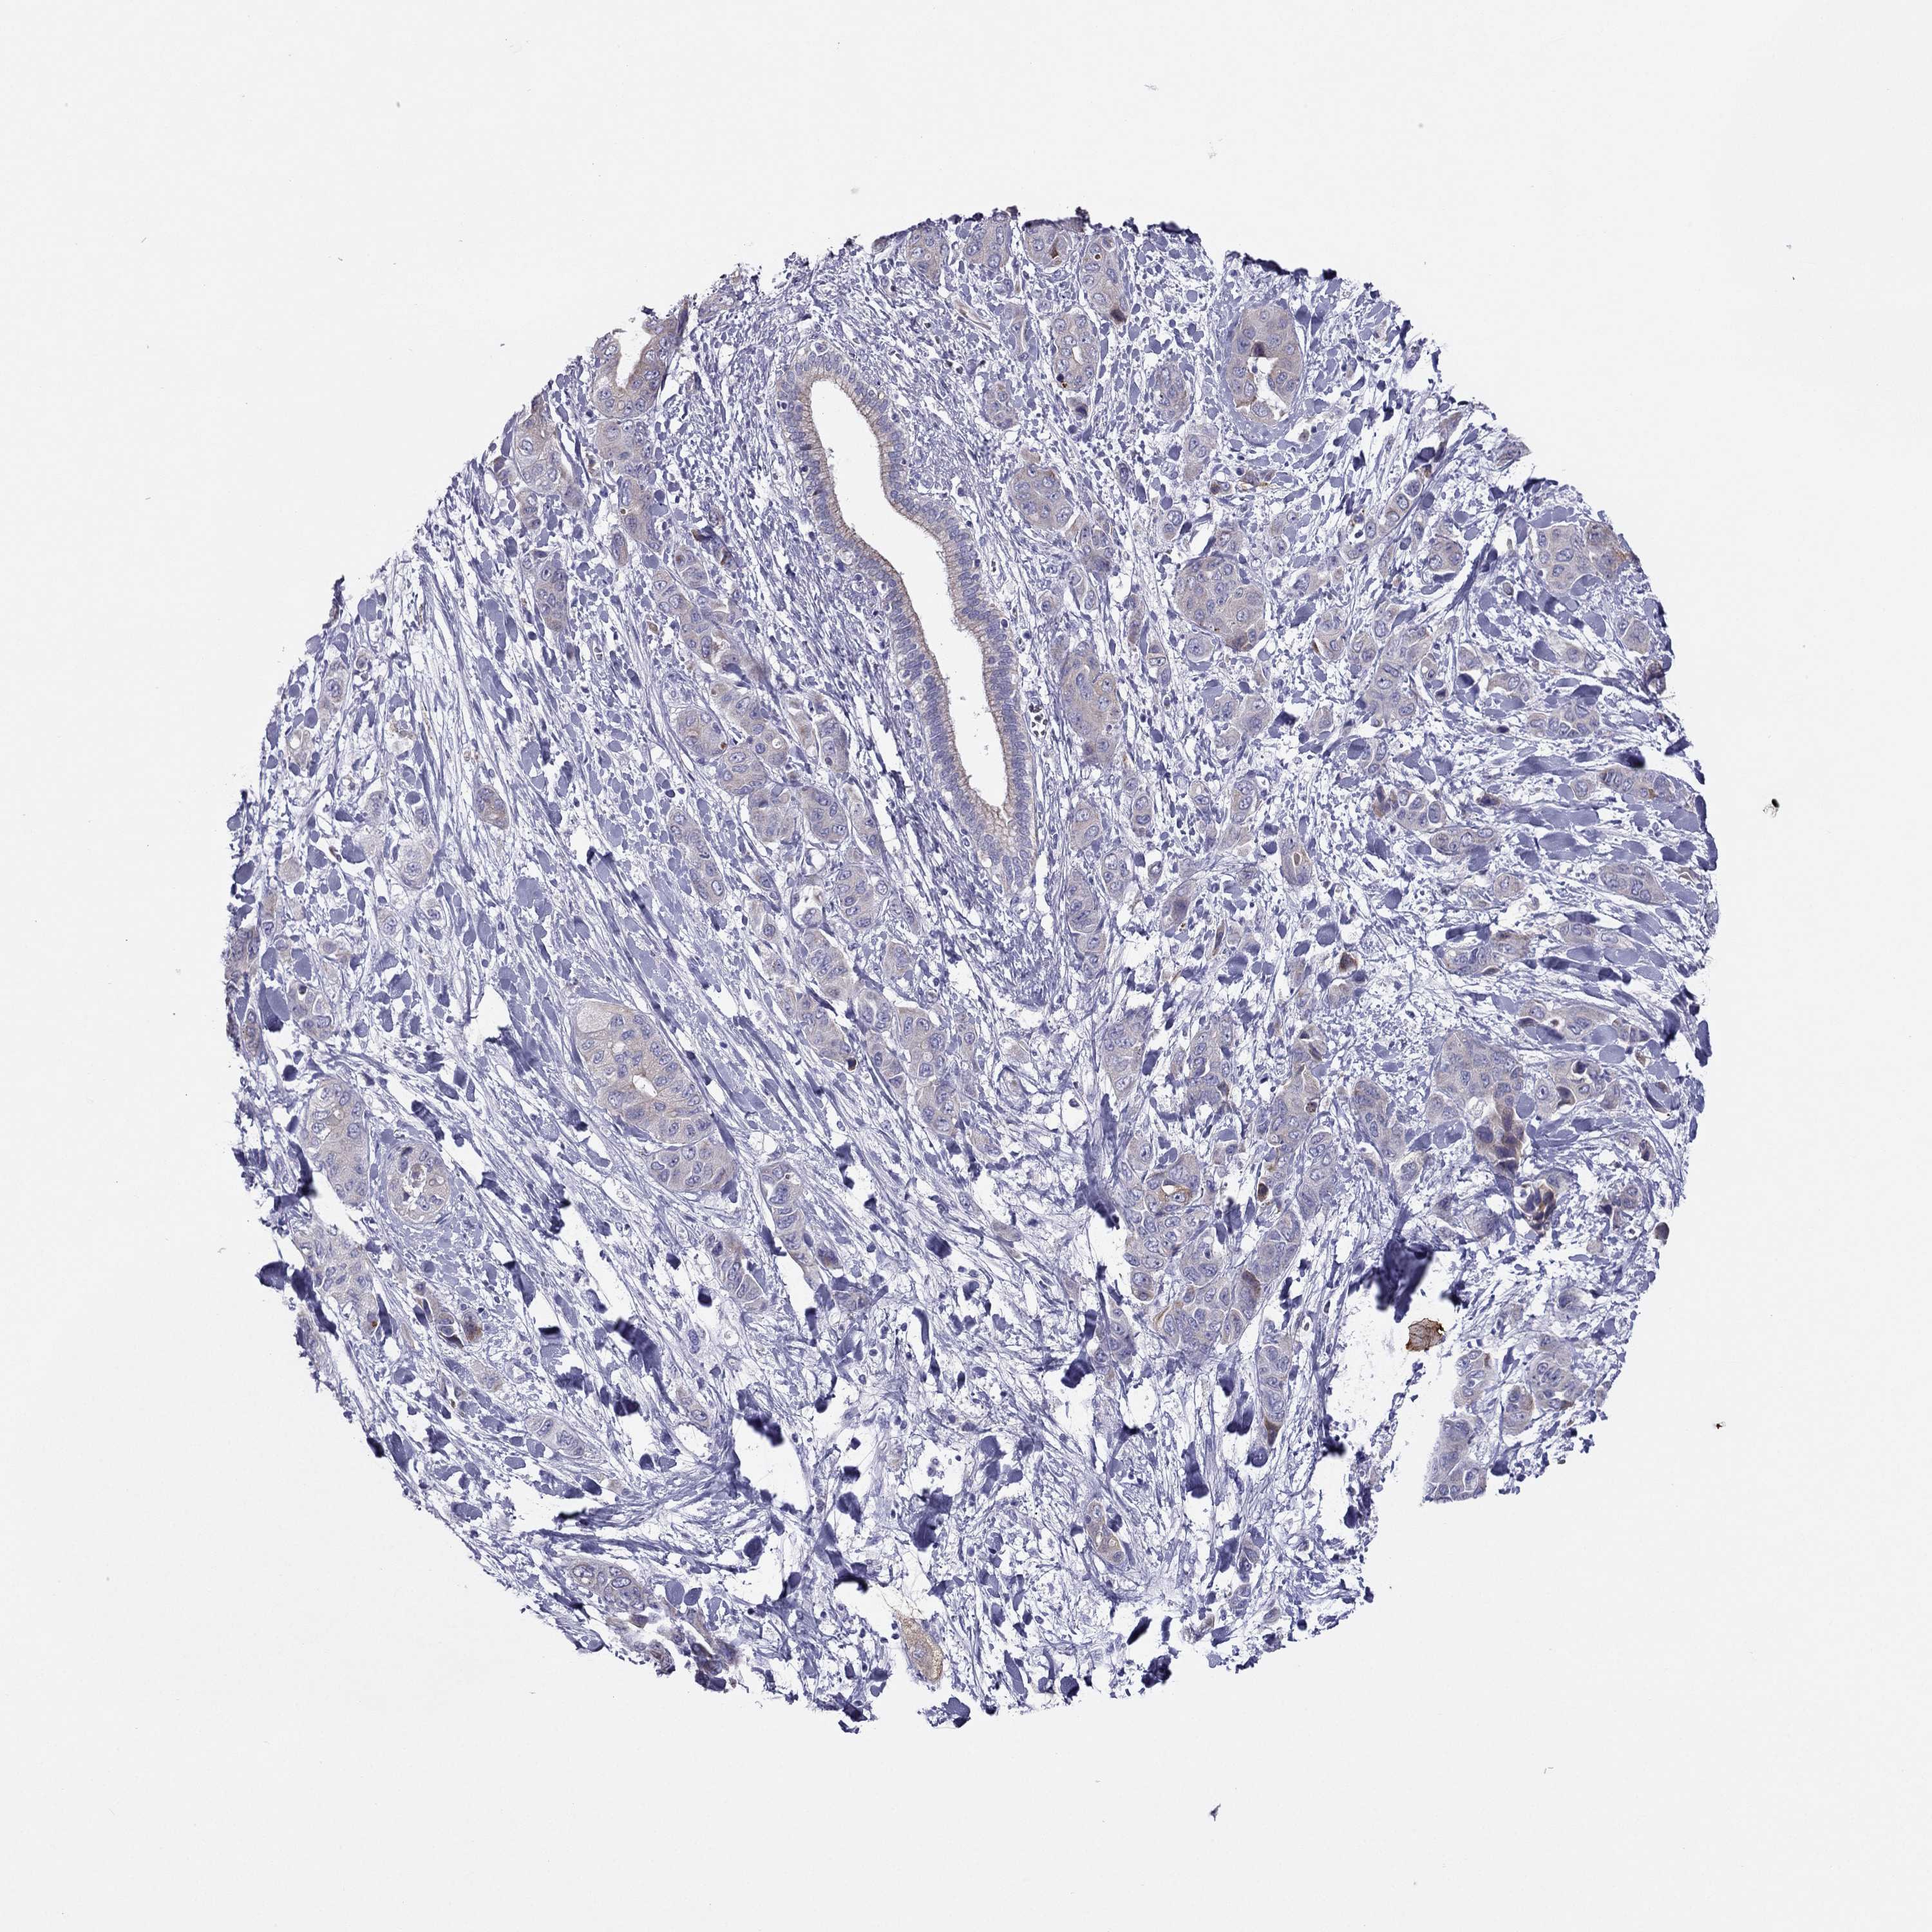

LIVER CANCER - Protein expressioni

A mouse-over function shows sample information and annotation data. Click on an image to view it in a full screen mode. Samples can be filtered based on level of antibody staining by selecting one or several of the following categories: high, medium, low and not detected. The assay and annotation is described here.

Note that samples used for immunohistochemistry by the Human Protein Atlas do not correspond to samples in the TCGA dataset.

Antibody stainingi

Antibody staining in the annotated cell types in the current human tissue is reported as not detected, low, medium, or high, based on conventional immunohistochemistry profiling in selected tissues. This score is based on the combination of the staining intensity and fraction of stained cells.

Each image is clickable and will lead to virtual microscopy that enables deeper exploration of all samples and also displays staining intensity scores, fraction scores and subcellular localization as well as patient and tissue information for each sample.

Antibody HPA078602

Staining

High

Medium

Low

Not detected

Intensity

Strong

Moderate

Weak

Negative

Quantity

>75%

75%-25%

<25%

None

Location

Nuclear

Cytoplasmic/membranous

Cytoplasmic/membranous,nuclear

Carcinoma, Hepatocellular, NOS

Cholangiocarcinoma

Adenocarcinoma, NOS